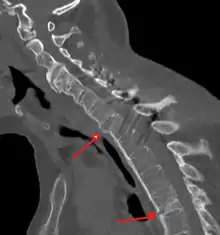

Imaging

X-rays

The earliest changes demonstrable by plain X-ray shows erosions and sclerosis in sacroiliac joints. Progression of the erosions leads to widening of the joint space and bony sclerosis. X-ray spine can reveal squaring of vertebrae with bony spur formation called syndesmophyte. This causes the bamboo spine appearance. A drawback of X-ray diagnosis is the signs and symptoms of AS have usually been established as long as 7–10 years prior to X-ray-evident changes occurring on a plain film X-ray, which means a delay of as long as 10 years before adequate therapies can be introduced.[24]

Options for earlier diagnosis are tomography and MRI of the sacroiliac joints, but the reliability of these tests is still unclear.

Lateral X-ray of the mid back in ankylosing spondylitis

Lateral X-ray of the neck in ankylosing spondylitis

X-ray showing bamboo spine in a person with ankylosing spondylitis

CT scan showing bamboo spine in ankylosing spondylitis

T1-weighted MRI with fat suppression after administration of gadolinium contrast showing sacroiliitis in a person with ankylosing spondylitis